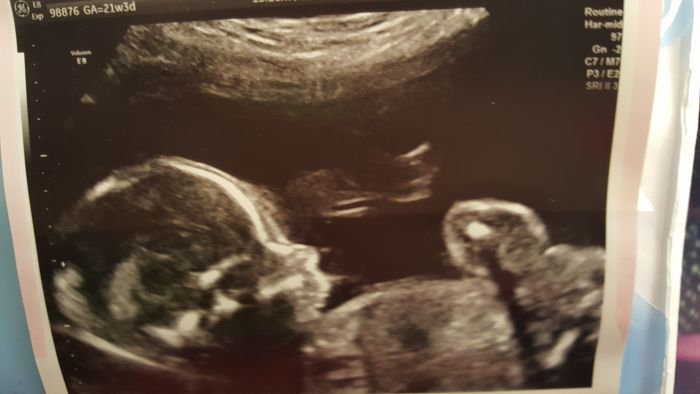

Za námi je druhý screening ve 22 týdnu a vše dopadlo na výbornou

.Jsem strašně šťastná a hrozně se mi ulevilo. Jo a čekáme chlapa s aktuální váhou 453g.Tuto informaci ještě zpracovávám...U manžela je to první kluk v rodině...